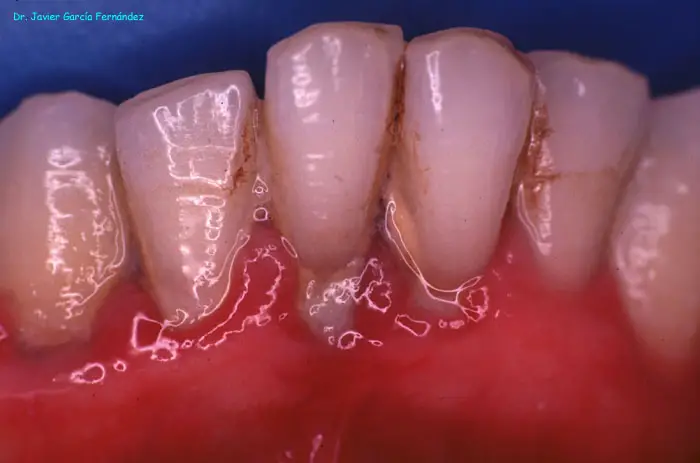

Atlas of Surgical Techniques in Periodontics. Chapter I. Diagnostic of Peridontal Diseases. Classification. Atlas de Técnicas Quirúrgicas en Periodoncia. Cap. I. Classification.

De la Salud a la Enfermedad Periodontal

image017